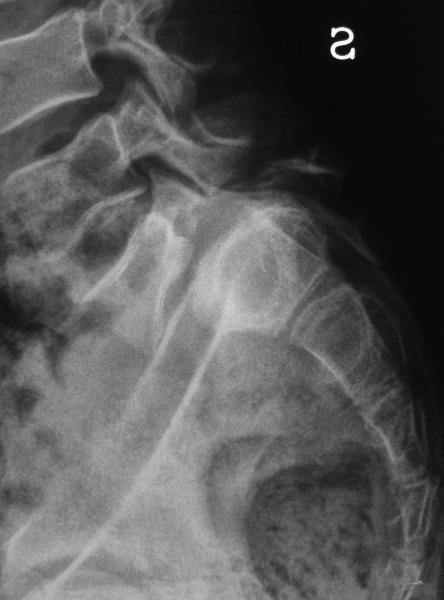

Gli esiti di malattie reumatiche o settiche dell’ articolazione sacroiliaca, se di una certa gravità, possono comportarne una limitazione dell’articolarità, indispensabile nella fase espulsiva del parto, nei movimenti di nutazione, per portare posteriormente il coccige e rendere di dimensioni adeguate il diametro antero-posteriore dello stretto inferiore.

Gli esiti delle fratture e delle fratture-lussazioni di bacino, specialmente di quelle non trattate correttamente, possono essere causa di un restringimento del canale del parto a tutti i livelli. Negli ultimi anni il trattamento di queste lesioni traumatiche, con lo studio di vie di accesso dedicate e con strategie condivise di osteosintesi, tende alla ricostruzione precisa dell’anatomia regionale, rendendo così possibile un successivo parto per vie naturali. Una particolare attenzione deve essere rivolta comunque alla presenza di mezzi di sintesi che ostacolino l’articolarità delle sacro-iliache, o che blocchino la sinfisi pubica: queste condizioni possono costituire infatti una indicazione relativa al taglio cesareo.